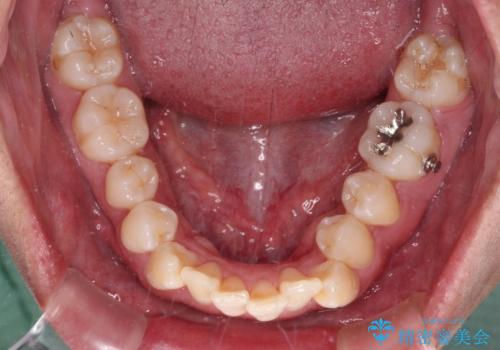

- 八重歯と飛び出している前歯を気にして来院された患者様です。

歯列としてはインビザラインでもワイヤー矯正でも対応できるものでしたが、上顎の八重歯や下顎小臼歯の捻転といったインビザラインでは時間のかかってしまう歯列不正が認められたため、補助装置やワイヤー矯正を治療当初に使用することで、インビザラインによる治療をスムーズに行えるように計画しました。

インビザラインは得意・不得意の差がはっきりとしているため、ワイヤー装置などをうまく活用することで、治療期間を短縮するとともに、より理想的な仕上がりを達成することができます。